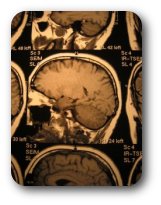

Os pacientes com aneurisma cerebral não roto apresentam dificuldade de diagnóstico por parte do médico. Os aneurismas não rotos não dão dor de cabeça. Algumas vezes apresentam-se como pequenas isquemias cerebrais ou queda da pálpebra. O especialista experiente deverá solicitar uma angiografia cerebral digital ou uma angiografia por ressonância magnética. Somente nos aneurisma muito grandes podemos fazer diagnóstico dos mesmo com uma tomografia computadorizada do encéfalo.

O diagnóstico de suspeição é feito pela história que o paciente conta quando o aneurisma é roto. Muitas vezes o paciente já chega em coma ao hospital. Cabe ao médico solicitar uma tomografia computadorizada do encéfalo que deve demonstrar sangue no espaço subaracnóide ou hematoma cerebral (coágulo dentro do cérebro).